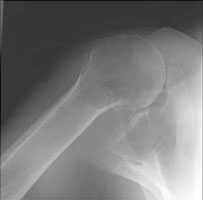

- Click on the image for a larger versionAAP radiograph of the shoulder. This shows marked overlap of the humeral head and the glenoid.